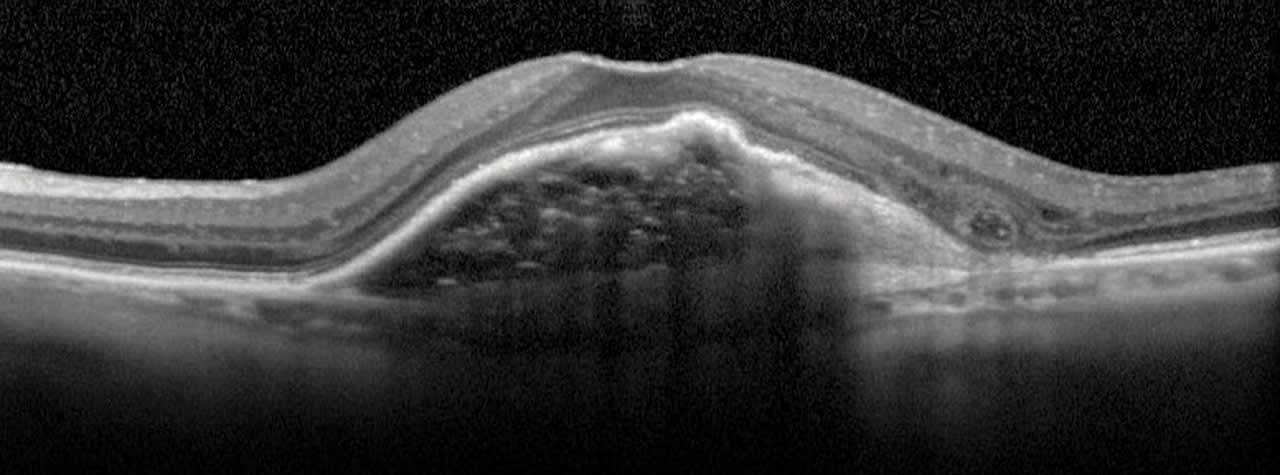

Outer retinal tubulation (ORT) is another instance where OCT provides prognostic value. ORT are tubular structures typically found in the outer nuclear layer in advanced AMD4 and are the scrolling of the external limiting membrane and photoreceptor inner segments, the result of restructuring of degenerative photoreceptor cells. They are easily identified by the hyperreflective band and hypo-reflective cavity (Figure 10). In the presence of ORT, the prognosis for recoverable vision is very unlikely.5